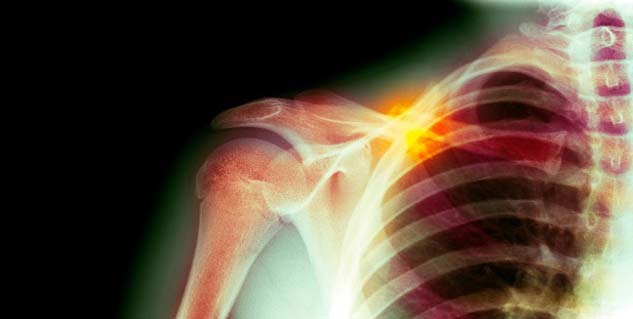

शरीर में कंधे की हड्डियों में कैंसर होना सामान्य है। कंधे में कई तरह के बोन कैंसर हो सकते हैं इसके कई लक्षण होते हैं। इन लक्षणों के जरिए कंधे की हड्डियों कैंसर का पता लगाया जाता है। कंधे की हड्डियों में कैंसर के कोई एक लक्षण नहीं होते हैं, लेकिन सबसे आम लक्षण दर्द होना है। जब कंधे की हड्डियों में ट्यूमर की शुरुआत होती है तो लगातार दर्द बना रहता है। इसके साथ अन्य लक्षण भी होते हैं आइए जानें उनके बारे में-

कंधे के पास बांह पर कभी-कभी सूजन आ जाती है। यह कंधे में बोन कैंसर होने पर सबसे ज्यादा देखे जाने वाला लक्षण है। ट्यूमर व फैक्चर के कारण आस-पास के ऊतकों में सूजन की समस्या होती है।

लालिमा

अगर दर्द के साथ रोगी के उस स्थान पर लालिमा भी है तो यह बोन कैंसर का बहुत बड़ा लक्षण हो सकता है। अगर कंधे के आस-पास बिना किसी वजह से लालिमा है तो डॉक्टर से एक बार सलाह जरूर लेना चाहिए।